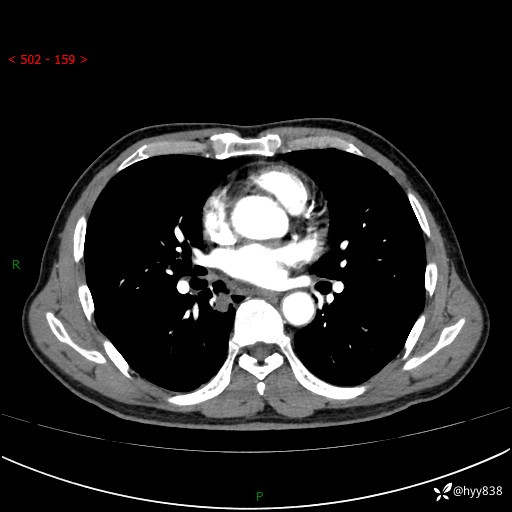

胸部CT平扫+增强